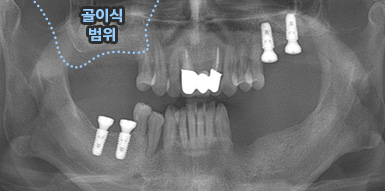

치조골 이식술이란?

치주염 등으로 치조골(잇몸뼈)의 양이 부족한 경우

치조골 이식술을 통하여 충분한 뼈의 양을 확보한 후

임플란트를 식립합니다.

뼈의 밀도가 치밀하고 단단하며, 양이 충분할수록 임플란트의 성공률이 높아집니다.

청담네오플란트는 풍부한 경험의 의료진이 치조골 이식술을 통해 치조골을 적절한 양과

밀도로 재생시킨 후 임플란트를 식립합니다. 뼈의 흡수가 심하지 않아 적은 양의

치조골 이식을 하는 경우 임플란트 식립을 동시에 진행할 수 있지만, 뼈의 흡수가

심하여 많은 양의 치조골 이식이 필요한 경우 치조골 이식술을 먼저 진행한 후,

치조골이 재생되면 임플란트를 식립하여 보다 정밀하고 안전한 시술 결과를 얻을 수 있습니다.

상악동은 윗턱뼈 내부의 구조물로서 개개인에 따라 생김새가 다릅니다.

상악동의 바닥이 잇몸뼈 방향으로 많이 내려온 경우, 임플란트를 식립하기에

잇몸뼈가 부족하게 됩니다. 이러한 경우 상악동 내부로 뼈이식을 하는

상악동 거상술이 필요하게 됩니다.